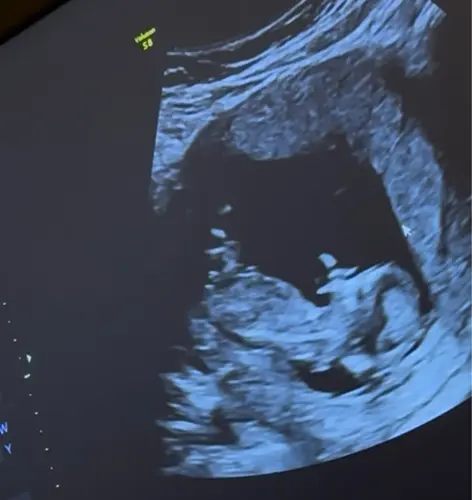

Is dit duidelijke een meisje? Door de nub dachten we namelijk eerst een jongen